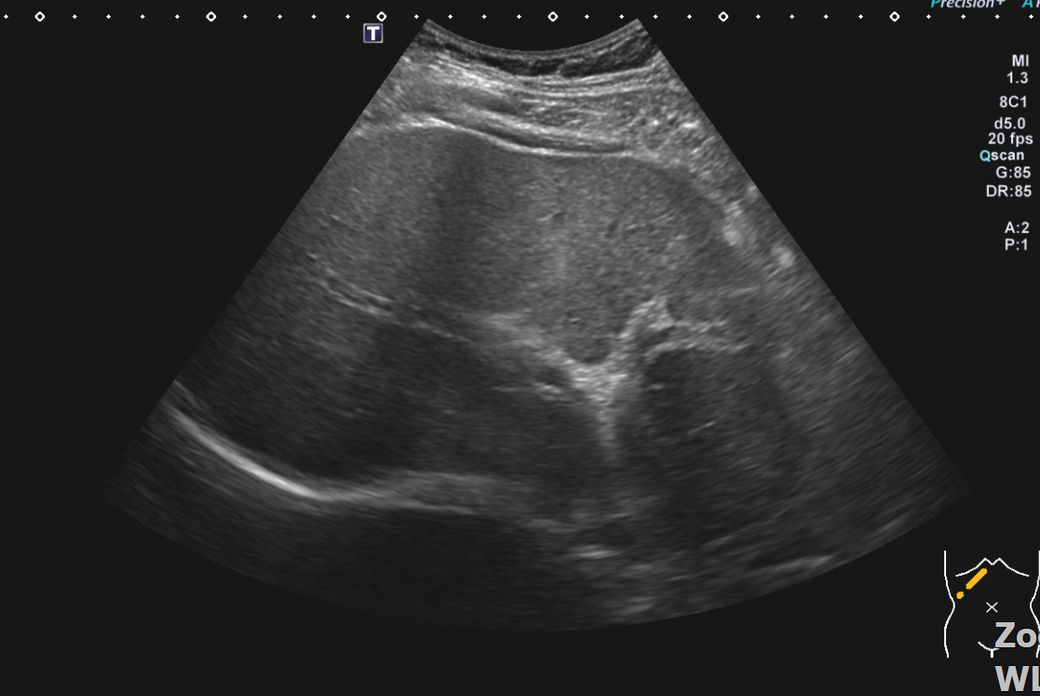

복부초음파 신장 물혹 보이나요? 사진올려봐요

신장물혹 0.6cm mri에는 나오는데 복부초음파에는 소견이없어서요

• 2번 째 사진

올려주신 사진 중 우측 신장이 찍힌 영상은 한 장이며 단면 영상만으로는 물혹 유무를 확인할 수 없습니다.